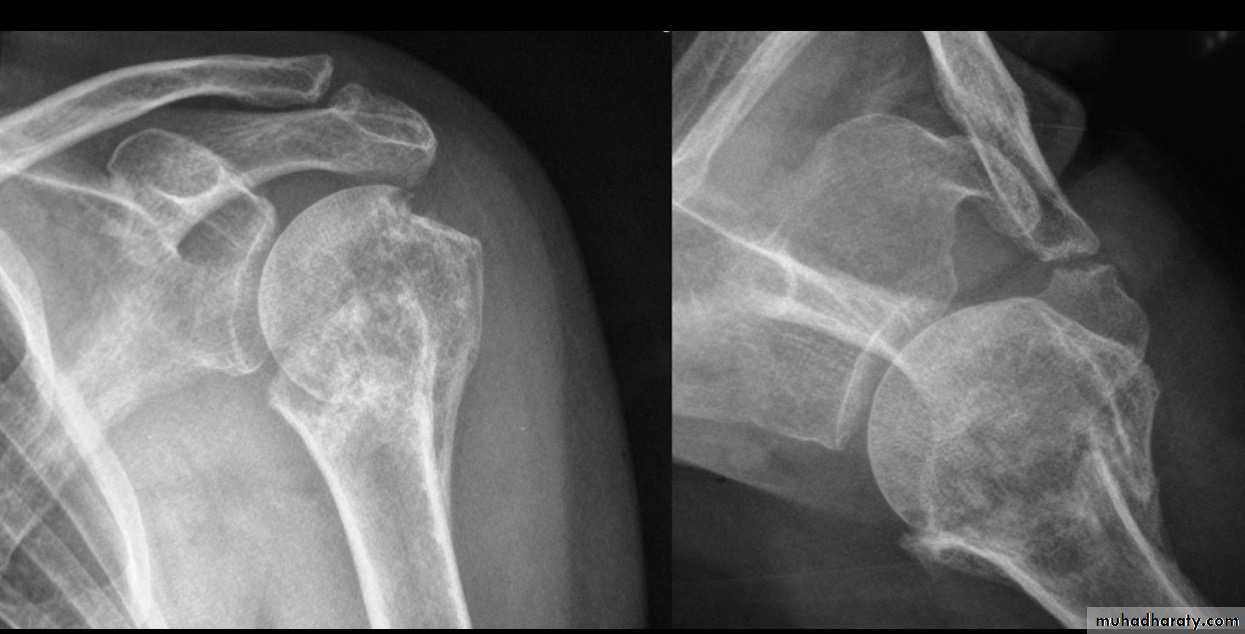

FOUR PART FRACTURE

32

X RAY

33

CT

34

TRATMENT IN YOUNG

35

ARTHROPLASTY